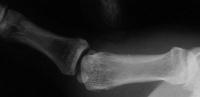

Not all need repair. This patient had an injury associated with rotation of the avulsion fracture. This often indicates a combination of fracture and ligament tear. However, the joint was stable, and had a good result from splinting alone. The bottom film shows the expected asymptomatic fibrous nonunion.